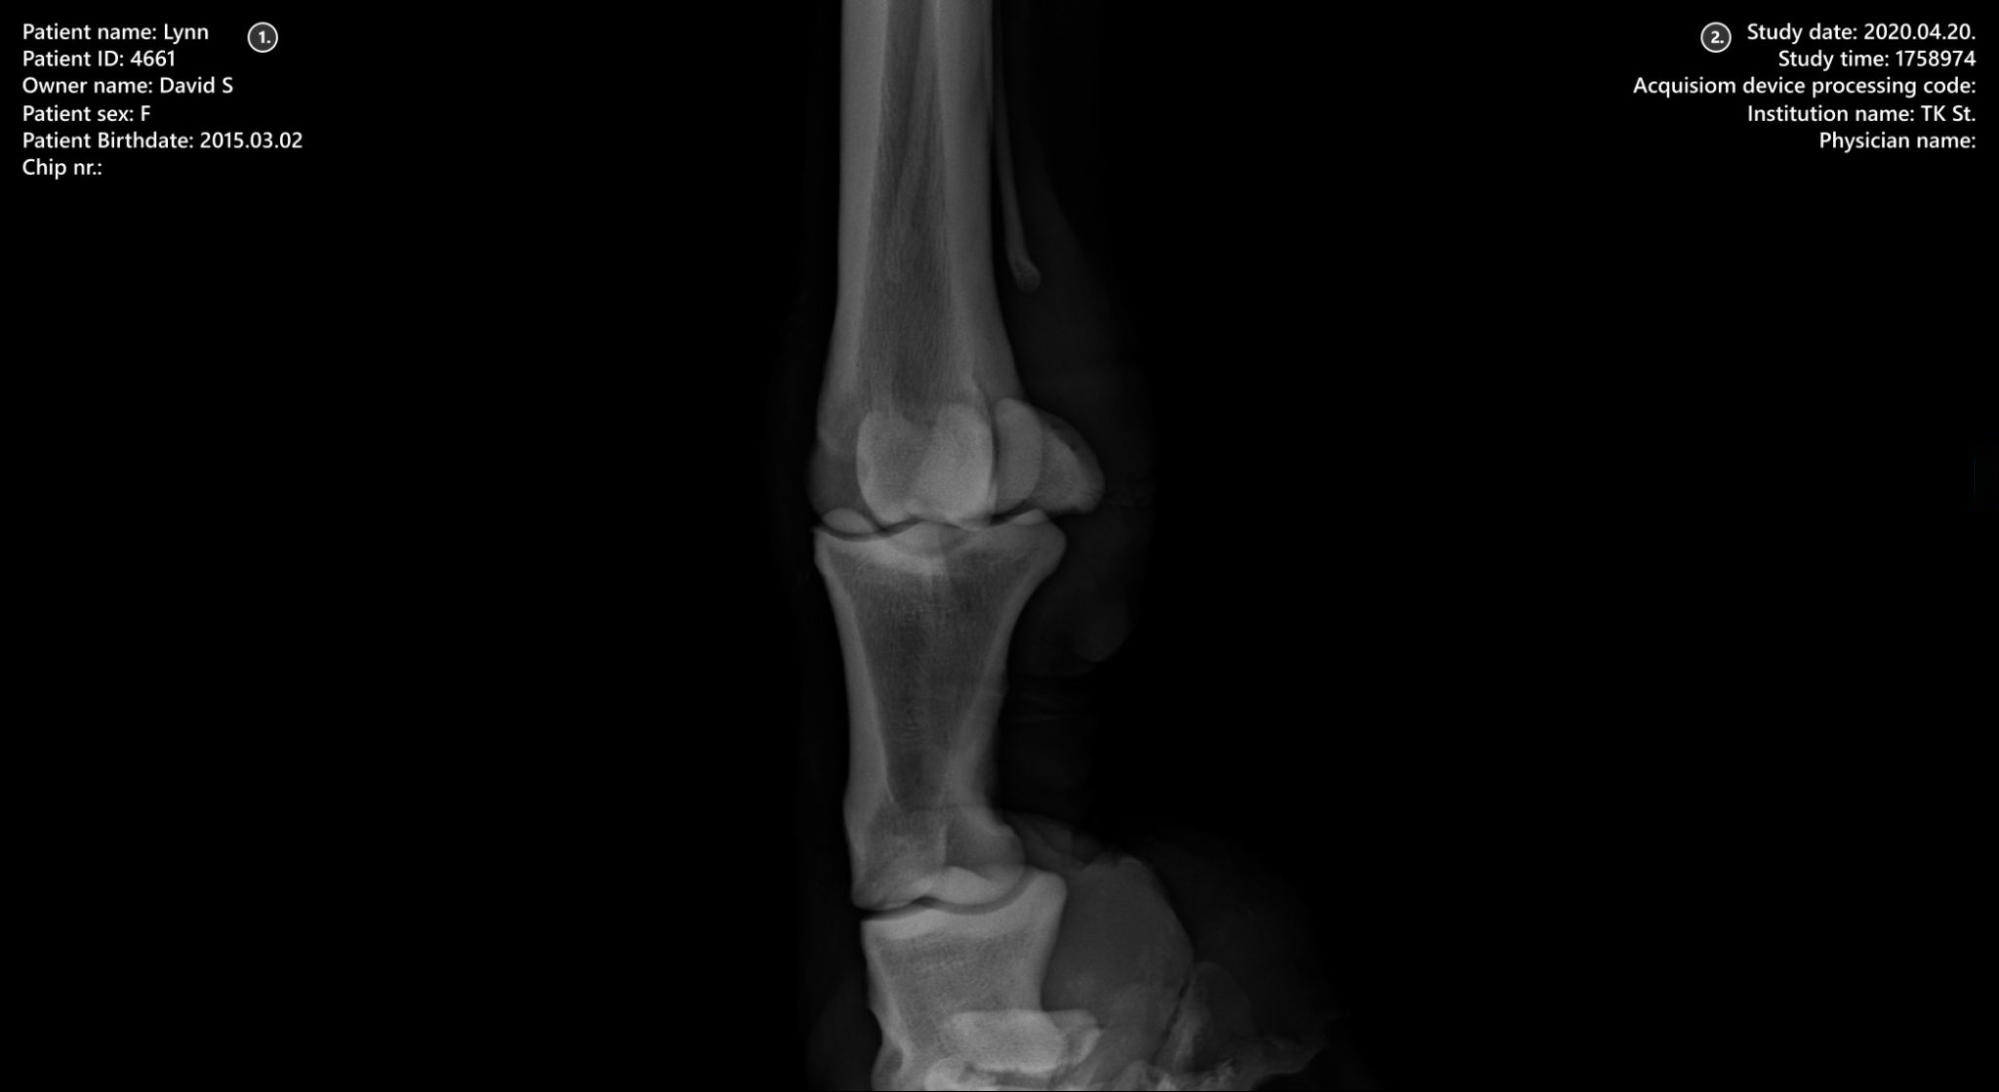

The VisioVIEW Viewer is a dedicated DICOM Viewer capable of displaying 2D monochromatic and color DICOM images. It supports static DICOM images as well as dynamic sequences of frames and slices. In addition, the VisioVIEW Viewer supports MPEG-2/MPEG-4 compressed video files with specific video playback controls.

Patient information

Study information